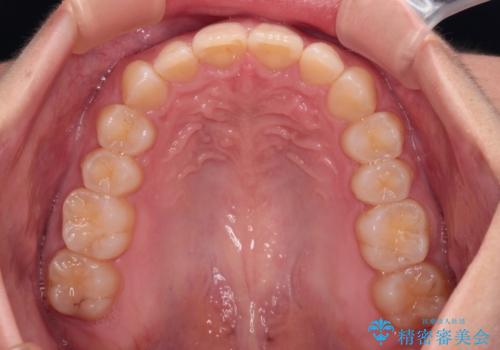

- 上の前歯の出っ歯と前歯の深い咬み合わせを治したいとのことで来院された患者様です。

上顎の歯は後方移動とIPR(歯と歯の間を削る)によって口元が引っ込むように、下顎は歯列全体の拡大とIPRによって上顎とバランスよく咬み合うように設計し、インビザラインにより治療を行うこととしました。

上顎歯列の後方への移動量が多く、右側の奥歯の咬み合わせを改善する必要もあったため、治療には長期間を要しました。